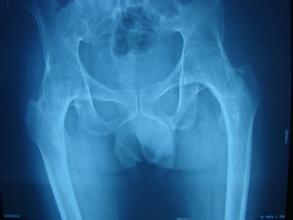

治疗强直性脊柱炎的过程是一个漫长的过程,因为此病多由遗传而得,病因复杂,非常难以治疗。不过很多病人并没有正确的认识到这一点,而是有一种浮躁的情绪,强直性脊柱炎心理调节也很重要,在治疗强直性脊柱炎之前要先消除自己的心理障碍。

强直性脊柱炎的病因较为复杂,因此治疗强直性脊柱炎的时间非常长,也很难彻底 。病人必须对此病有一个清醒的认识,在治疗上能够积极配合大夫。通过正规的治疗方法来减轻自己的痛苦,控制症状。急于求成的结果往往是不好的。